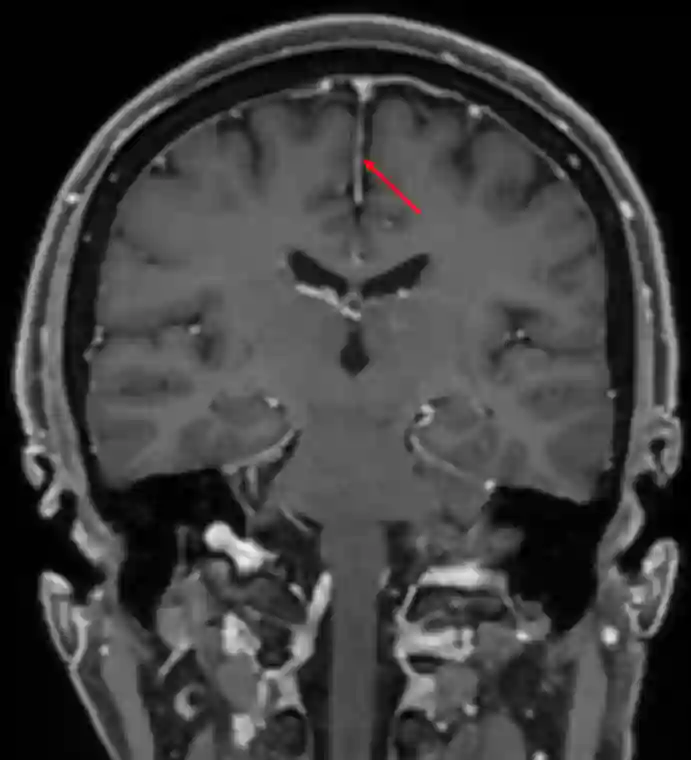

Falx cerebri im MRI

Falx cerebri in einem koronaren MRI Bild (T1 Sequenz mit Kontrastmittel)